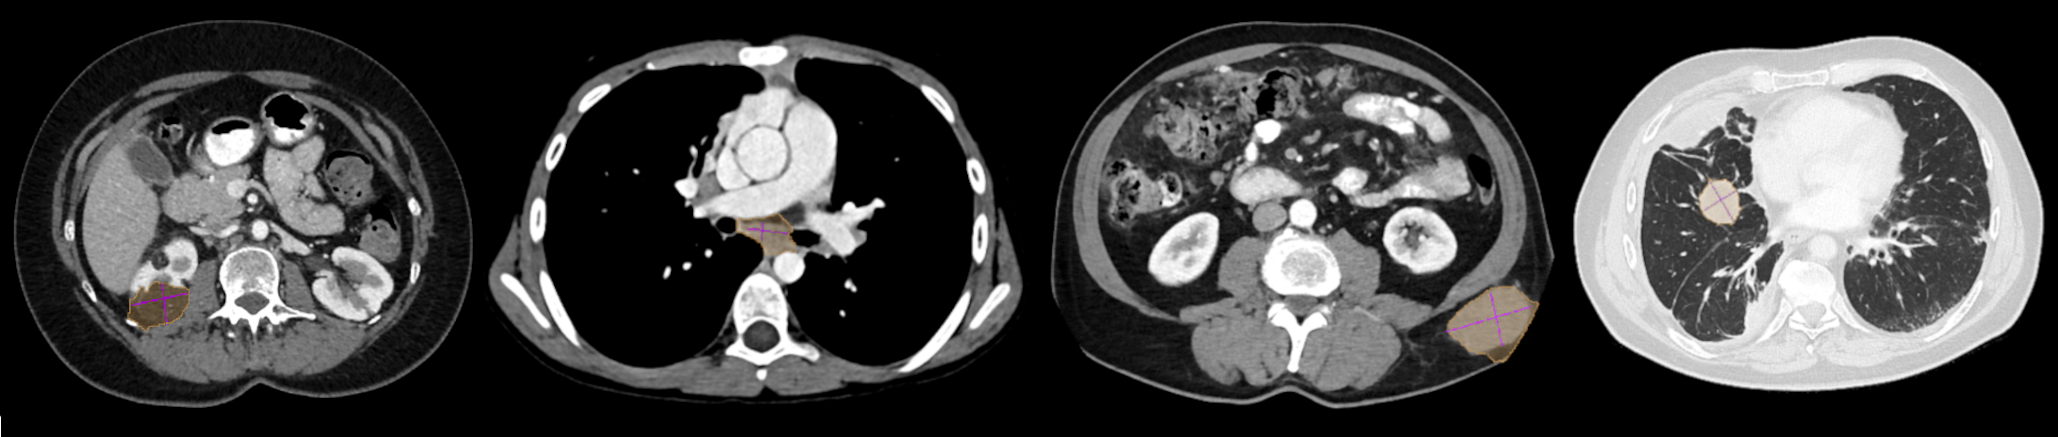

Refer to caption

Figure 2: Examples of GrabCut pseudo-masks. From left to right, a kidney lesion, mediastinal lymph node, subcutaneous mass, and lung lesion. Note how GrabCut tends to oversegment (orange mask \blacksquare) into healthy tissues compared to the reference measurements (purple lines \blacksquare). Lung lesions are visualized using Window Level: -500 HU, Window Width: 1400 HU. Lesions outside the lungs with WL: 350 WW: 40.